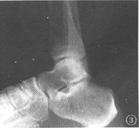

踝關節又叫距骨小腿關節,由脛腓骨下端夾騎於距骨之上而成。脛骨下端向內和向下突出的部份分別稱為內踝和後踝,腓骨下端的突出部份則被稱為外踝。內、外和後踝共同構成踝穴。內踝較外踝短,故踝關節易內翻受傷。距骨位於踝穴之內,其關節面前寬後窄,其從前向後的凹陷與脛骨下端的凸面共同組成一個類似滑車的關節,便於踝關節的屈伸活動,又可防止踝關節向後脫位,起到穩定踝關節的作用,踝關節囊前後較松,而兩側較緊。踝關節的四周有韌帶加強,特別是內外兩側更是如此。內側有三角韌帶,起於內踝,呈扇形向下止於舟骨、距骨和跟骨。在外側有三個獨立的韌帶,前方為距腓前韌帶,中部為跟腓韌帶,後方為距腓後韌帶,起於外踝,分別向前、下、後止於距骨和跟骨。外側的韌帶較內側的三角韌帶弱,加之內踝較短,臨床上易發生內翻而損傷外側韌帶。

踝關節既負重,又活動,韌帶又多,相對的關節面也多,容易發生關節扭傷、韌帶損傷、骨折或關節軟骨損傷。韌帶、軟骨本身血運營養差,損傷後不易癒合,易形成腫脹和慢性疼痛,影響踝關節負重,行走困難。因此出現踝關節損傷後切忌疏忽誤治,延誤病程,遺留一些慢性症狀。